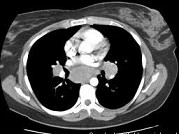

- 单项选择题女,33岁, 咳嗽,乏力, 低热,皮肤有结节, 结合CT图像,最可能的诊断是 ( )

D、结节病